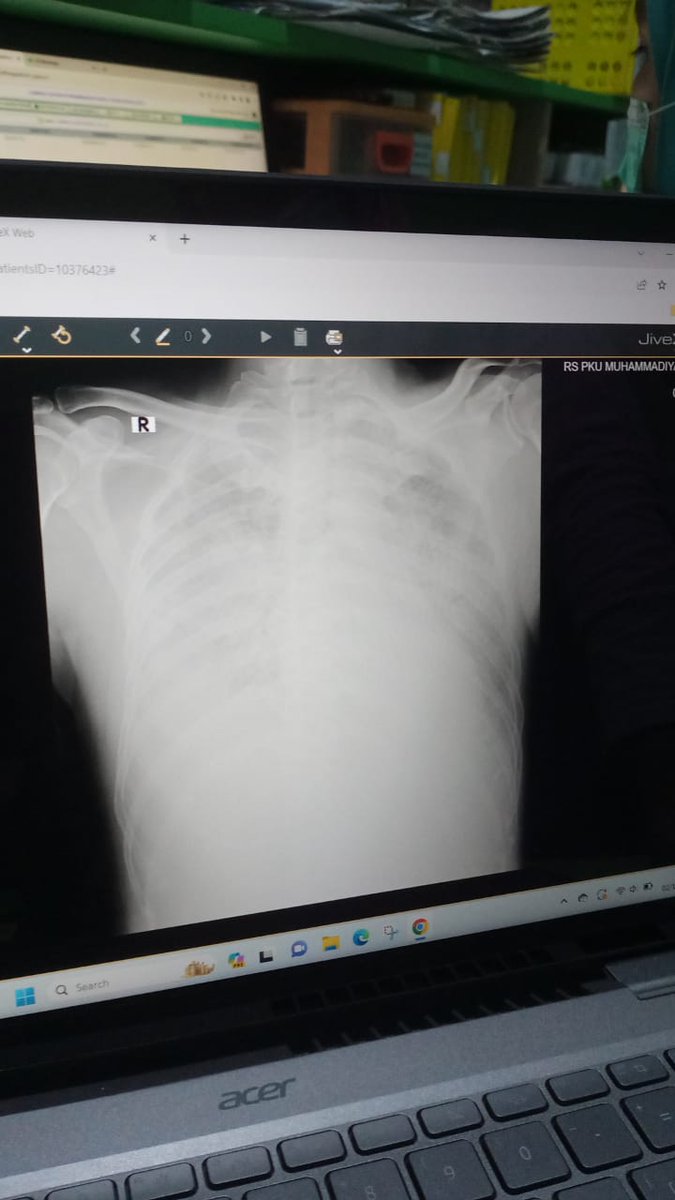

well.. ini cairan paru paru ayahku, he never smoke tapi kena dampak dari orang sekitarnya yang merokok. they took my dad’s life..